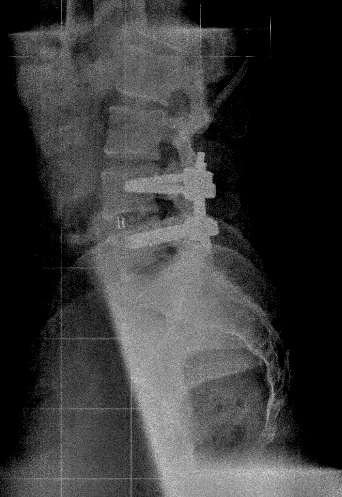

En el TLIF MIS (Transforaminal Lumbar Interbody Fusion Minimal Invasive Surgery) se obtiene el mismo resultado que el TLIF clásico o abierto, con la diferencia que sólo se realizan dos incisiones paramedianas y no se separa la musculatura de sus anclajes osteoligamentosos. El postoperatorio es mucho mejor en el TLIF MIS que en una cirugía abierta, sin embargo muchas veces no se puede plantear TLIF MIS y hay que realizar TLIF «abierto», sobre todo en patología degenerativa avanzada cuando vamos a asociarlo con otras técnicas (Laminectomía lumbar o artrectomía bilateral para corrección de lordosis o listesis).

-XLIF (DLIF, LLIF), OLIF: El uso de XLIF se ha generalizado para el tratamiento de la escoliosis degenerativa lumbar y la corrección del balance sagital. Los niveles donde más suele emplearse son L2-L3 y L3-L4. El abordaje mínimamente invasivo en un flanco lateral del abdomen permite acceder al disco desde el espacio retroperitoneal, realizando una pequeña incisión en el psoas. La colocación de una prótesis de gran tamaño (comparada con otras técnicas como PLIF o TLIF) que ocupa todo el diámetro coronal de la vértebra permite una corrección del espacio intervertebral, recuperando la altura del disco originaria y la lordosis, lo que provoca una descompresión posterior indirecta sobre el ligamento amarillo al tensarlo de nuevo.

También puede tener su utilidad en el tratamiento del nivel adyacente como alternativa a ampliar la fusión vía posterior. La vía «clásica» obliga a reabrir la cicatriz y desconectar el sistema de artrodesis, colocar dos tornillos en el nivel añadido y una barra más larga. La herida reabierta tarda más en curar. Mediante la técnica XLIF podemos acceder al nivel adyacente y realizar una fusión posterior colocando una placa lateral y evitando «tocar» la artrodesis previa y la herida cicatrizada.